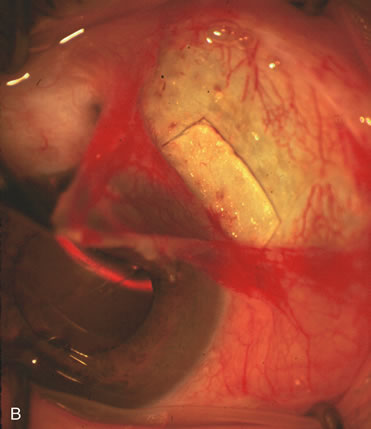

Fig. 4. Viscocanalostomy with deep sclerectomy and phacoemulsification. Nonpenetrating filtration procedures (NPFS) may be combined with phacoemulsification. Patients with mild disc damage and a history of limited topical drug therapy are the best candidates. Patients who require an IOP in the low teens are not good candidates for NPFS. By definition, NPFS is designed to lower IOP without penetrating into the anterior chamber, thereby avoiding the complications associated with trabeculectomy. Viscocanalostomy is intended to allow aqueous to percolate through a trabeculodescemetic membrane into a subscleral cavern created by the deep sclerectomy. The aqueous diffuses from the cavern into the dilated ostia of Schlemm's canal and into the episcleral venous plexus. A. Fashion a uniform 300-micron superficial scleral flap 1 mm into clear cornea. B. Construct a second 600-micron deep flap that facilitates the unroofing of Schlemm's canal, seen as the darker area. C. Use viscoelastic to dilate the ostia of Schlemm's canal. The major problem with viscocanalostomy is the eventual closure of the ostium decreasing flow to the episcleral plexus. D. Dissect the deep flap anteriorly into clear cornea creating the trabeculodescemetic membrane. This membrane is clearly seen between the scleral spur and the bend of the deep flap. The integrity of this membrane ensures the nonpenetrating portion of the surgery. Another problem with NPFS is the eventual fibrosis of this initially transparent membrane requiring goniopuncture. E. Deep sclerectomy gets its name from removal of the deep flap. Removal of this flap creates the potential subscleral space for accumulation of aqueous before it enters Schlemm's canal and exits the episcleral venous plexus. After removal of the deep flap, the superficial flap is sutured into place and conjunctiva closed. Approximately half of these procedures develop a shallow bleb.